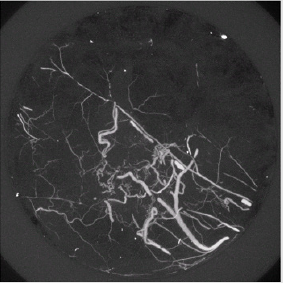

We used Sutent in this study as an anti-angiogenic compound to quantify the vascular normalization in response to two regimens. Sutent (SU11248, sunitinib malate, Pfizer, Inc., New York, NY, USA) is a small-molecule, multi-target tyrosine kinase inhibitor with high affinity for the PDGF and VEGF receptors [18]. Dual delivery of VEGF and PDGF-BB returned more mature vessel formation than either single growth factor. Sutent has demonstrated anti-tumor activity and inhibition of angiogenesis in clinical trials [19,20]. It was approved by the FDA in January of 2006 to treat renal cell carcinoma and imatigib-resistant Gastrointestinal Stromal Tumors (GIST). Imaging technology has advanced significantly over the last decade for drug research and clinical diagnoses. Various imaging modalities with proper imaging analysis methods have been utilized to reveal the function and anatomy of vascular structures in differing spatial and temporal resolutions [21,22]. Contrastenhanced CT is able to reconstruct three-dimensional (3-D) vascular structures with resolution of a few microns. In this study, the isotropic voxel dimension of all images in the vehicle and the treated groups was 16 m (Figure 1A & 1B).

Figure 1B: MIP demonstration of vascular remodeling in response to two-week Sutent treatment. A significant qualitative vascular structure alteration compared to a two-week vehicle is easily recognized. Entire vascular normalization in the tumor due to the Sutent compound (less sprouting, less tortuosity) is observed.